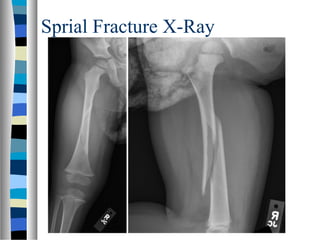

Sprial Fracture X-Ray

Spiral Fracture  AlsoCalled Torsion Fracture  Break Spirals Around the Bone  Common In a Twisting Injury  Can Only Be Caused If a Limb (Arm or Leg) Is Twisted in Such a Way That Causes the Bone to Break.

Spiral Fracture  Causedby Certain Types of Accidents – Especially in Sports, Especially Skiing  Abuse – Arm or Leg is Twisted by the Abuser

Causes Of SpiralFracture  In Skiing - skiers lock their feet into the skis in sturdy ski boots, if a ski breaks or the skier loses control and the ski rotates, the leg may be violently twisted in one direction, creating a textbook spiral fracture.  Spiral Fracture has become famous as a warning sign of abuse, especially in children, because the twisting motion necessary could be caused by something such as a parent or guardian grabbing and twisting the arm or leg of a child. When doctors see spiral fractures in children, it may set off warning bells.